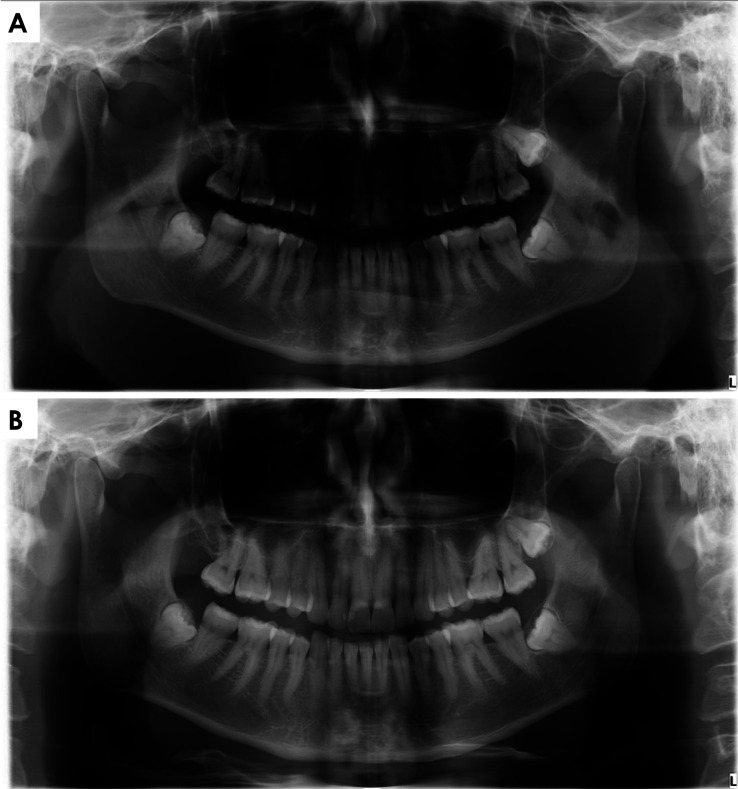

Results: Of the 1,088 panoramic radiographs evaluated, 69 displayed tongue positioning errors. Of these, 53 radiographs were from patients without access to the educational video, whereas only 16 were from patients who had received the video (P<0.05). Patients without video access were 2.07 times more likely to exhibit tongue positioning errors than those who had access. The other variables assessed (sex, age, scheduling method, and educational background) did not significantly influence tongue positioning errors (P>0.05).

Conclusion: Providing patients with an educational video on proper tongue positioning significantly reduced tongue positioning errors on panoramic radiographs.